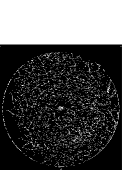

V-D Sensitivity analysis of threshold values of region features

The default threshold values of region features: e1=0.35subscript𝑒10.35e_{1}=0.35, r=2.2𝑟2.2r=2.2, s=0.53𝑠0.53s=0.53, e2=0.25subscript𝑒20.25e_{2}=0.25 are used in our work. In order to demonstrate the insensitivity of the proposed model to these threshold values, the variations in Acc𝐴𝑐𝑐Acc by varying e1subscript𝑒1e_{1}, e2subscript𝑒2e_{2}, r𝑟r and s𝑠s are given in Fig.10.(a), (b), (c) and (d). From Fig.10, it can be observed that the proposed model can maintain high segmentation accuracy on the DRIVE, STARE and CHASE_DB1 datasets as e1subscript𝑒1e_{1} varies in [0.2,0.4]0.20.4[0.2,0.4] or e2subscript𝑒2e_{2} varies in [0.15,0.3]0.150.3[0.15,0.3]; For r𝑟r and s𝑠s, the proposed model can maintain high segmentation accuracy as r𝑟r varies in [2,6]26[2,6] or s𝑠s varies in [0.4,0.6]0.40.6[0.4,0.6]. From the above observation, it can be seen that the proposed model is not sensitive to these threshold values of region features when they change in a relatively large range.

Figure 10: Sensitivity analysis of threshold values of region features used in the work. (a) Variations in mean segmentation accuracy by varying e1subscript𝑒1e_{1} when r=2.2𝑟2.2r=2.2, s=0.53𝑠0.53s=0.53, e2=0.25subscript𝑒20.25e_{2}=0.25. (b) Variations in mean segmentation accuracy by varying e2subscript𝑒2e_{2} when r=2.2𝑟2.2r=2.2, e1=0.35subscript𝑒10.35e_{1}=0.35, s=0.53𝑠0.53s=0.53. (c) Variations in mean segmentation accuracy by varying r𝑟r when e1=0.35subscript𝑒10.35e_{1}=0.35, s=0.53𝑠0.53s=0.53, e2=0.25subscript𝑒20.25e_{2}=0.25. (d) Variations in mean segmentation accuracy by varying s𝑠s when r=2.2𝑟2.2r=2.2, e1=0.35subscript𝑒10.35e_{1}=0.35, e2=0.25subscript𝑒20.25e_{2}=0.25.